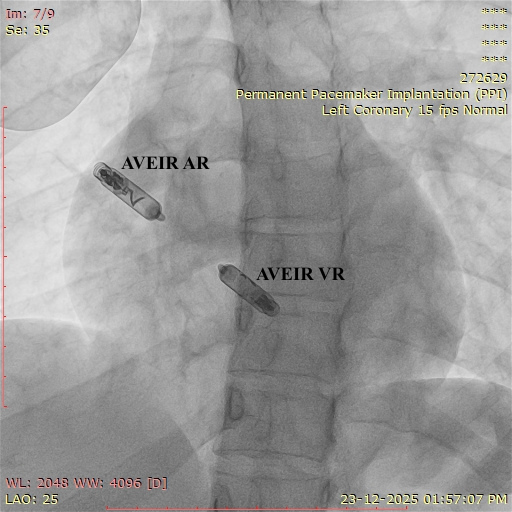

The Abbott AVEIR™ DR is the world’s first dual-chamber leadless pacemaker designed to treat abnormal heart rhythms using two miniature devices implanted directly inside the heart — one in the right atrium and one in the right ventricle. Unlike traditional pacemakers, this innovative system works without wires, chest pockets, or surgical incisions.

The system includes two small catheter-delivered devices:

AVEIR AR – placed in the right atrium

AVEIR VR – placed in the right ventricle

Using advanced implant-to-implant (i2i) wireless communication, both devices coordinate on a beat-to-beat basis to maintain natural heart rhythm and support dual-chamber pacing modes.